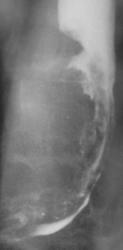

Иллюстрация 5, 6. В боковой проекции определяется концентрическое сужение нижней трети пищевода, выражено нависание интактной стенки пищевода в виде «кулис» над суженным участком – иллюстрация 7. Контуры сужения неровные и нечеткие. Атипически перестроенный рельеф импергнирован бариевой взвесью.